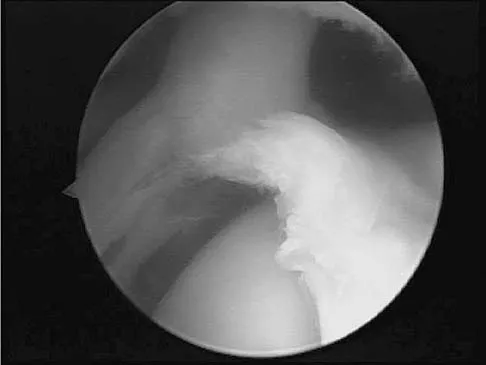

The view from an anterosuperior portal of the right shoulder shown in Figure 12 reveals which of the following findings?

Explanation